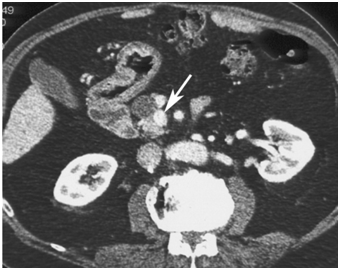

Although there is a potential "blind-spot" at the splenic hilum, a high sensitivity has been obtained. A recent single-centre prospective study showed a sensitivity of 93% and a specificity of 95% in localization of intra-pancreatic lesions. EUS could detect all tumors visualized by every other conventional technique, thus questioning the need for the rest imaging modalities (Figure 6–8).44–48

Figure 7a CT scan showing an insulinoma (white dot pointed to by yellow arrow) in the body of the pancreas (P with arrows pointing to the body and tail of the pancreas). The stomach (S with green lines up and down) has air (black) and fluid (darker gray) with it (stomach wall at end of lower green line). 42

Figure 7b CT scan showing insulinoma (white dot pointed to by yellow arrow) in junction of head and uncinate portions of pancreas. Just to the right of the insulinoma is the portal vein (white with "tail"–vein from the spleen joining it) carrying blood from intestine and pancreas to liver. 42